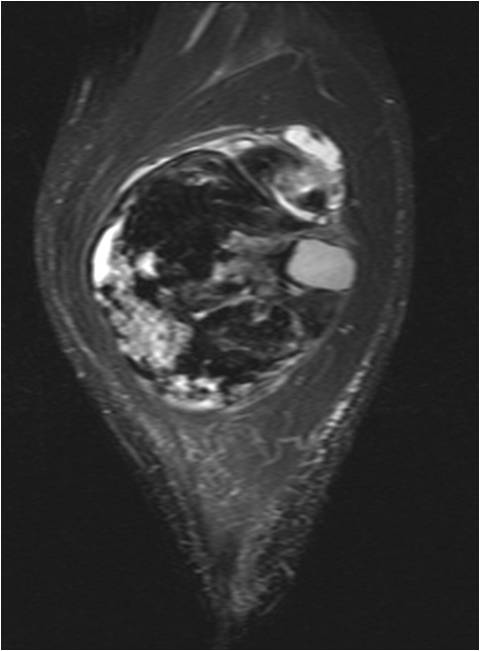

On radiographs, Low Grade Fibromyxoid Sarcoma presents as a discrete mass with soft tissue density without mineralization. MRI shows a well circumscribed heterogeneous mass, primarily hypo or isointense to muscles on T1-weighted image. The majority of tumors demonstrate heterogeneous signal intensity on T2-weighted images, correlating with the histological characteristics of low grade fibromyxoid sarcoma. Although 48 % of the patients demonstrate hyperintense signal and the rest of patients present admixed of hypo and Isointense signals (Fig. 1-5).

Fig. 3-5. MRI Axial (Fig. 3) and Coronal (Fig. 4) T2 –weighted fat-suppressed image heterogeneously high signal intensity areas admixed with hypo and isointense areas. T1-weighted post contrast fat-suppressed images (Fig. 5) show heterogeneous signal and enhancement within the tumor.